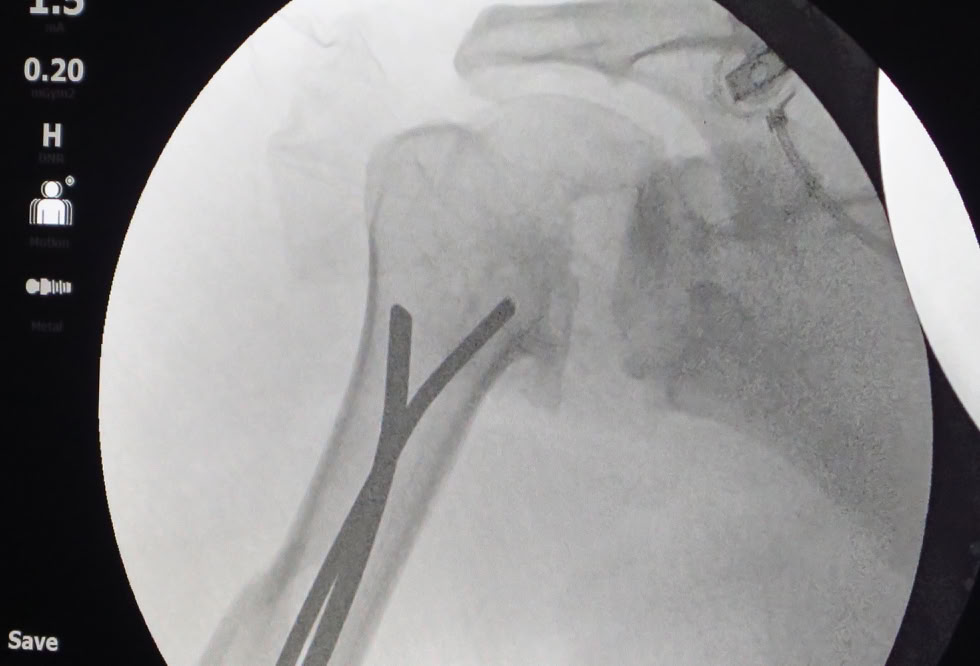

Recibimos la visita de un traumatologo que trabaja en un hospital de Duala y que se desplazó hasta Dschang para que le tratáramos nosotros las lesiones que sufrió al caerse por unas escaleras, “no se fiaba de sus compañeros de hospital”. Una fractura de la extremidad distal del radio que solucionamos con una reducción y estabilización con agujas K (no tenemos placas volares) con excelente resultado  y una fractura diafisaria de humero que solucionamos con unos clavos elásticos (no tenemos clavos de humero). El paciente estaba muy satisfecho a pesar de la parálisis radial que se produjo al fracturarse.